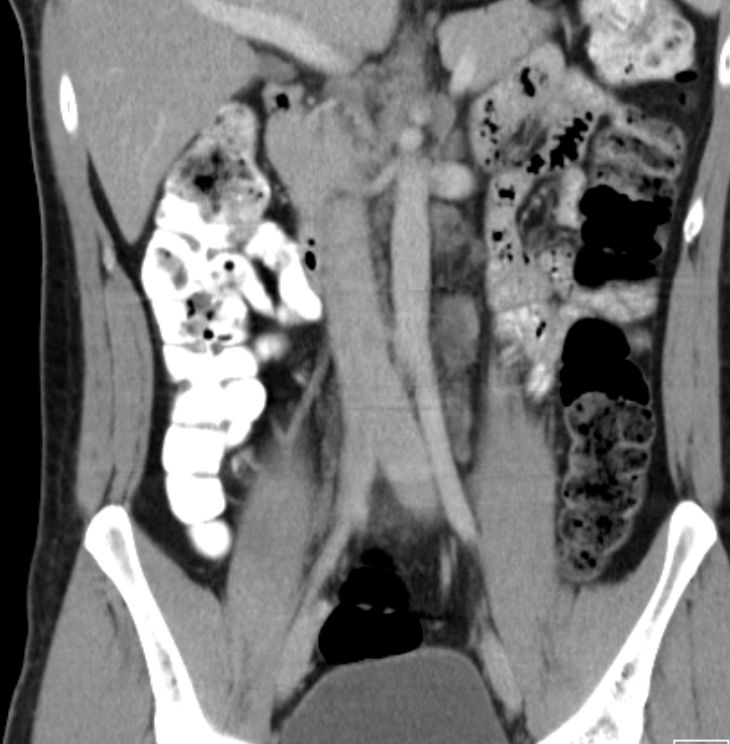

21mm große Lymphknotenmetastase links paraaortal unterhalb des Nierenstiels.![]() |

30-jähriger Mann mit einem 17mm großen reinen Seminom links.

Links paraaortal unterhalb des Nierenstils 3 bis 30mm große Lymphknotenmetastasen![]() | ||